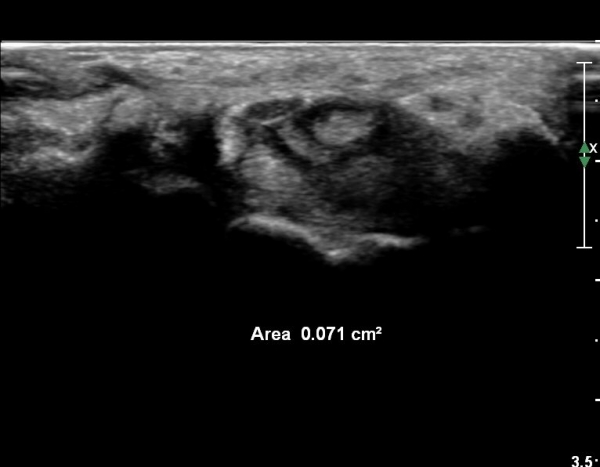

¾Æ·§ÆÈ ¸»´ÜºÎ Ⱦ´Ü¸é°Ë»ç¿¡¼­ ¼Õ°¡¶ô ±¼°î ÈûÁÙÀÇ ºñÈÄ¿Í ÈûÁÙ ½ÉºÎ¿¡ ¼ö¾×Àú·ù°¡ °üÂûµÈ´Ù(»çÁø 1).